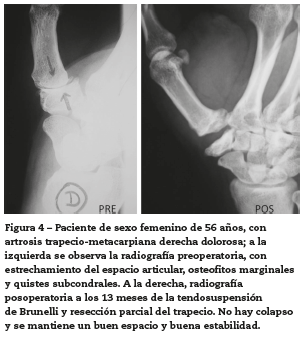

Para el primer grupo: 13 mujeres y 1 hombre, edad promedio de 59 años (41-74), estado radiológico en 19 manos con estadio 3 de Eaton y 2 con estadio 2, el dolor preoperatorio según la escala visual análoga era en promedio de 8,45 (7-9) y al seguimiento final 0,95 (0-2) (tabla 1).

En promedio, la movilidad en abducción fue de 33,8° y el arco de flexión de 33,5°. Todos estaban satisfechos con la cirugía (figs.4 y 5).